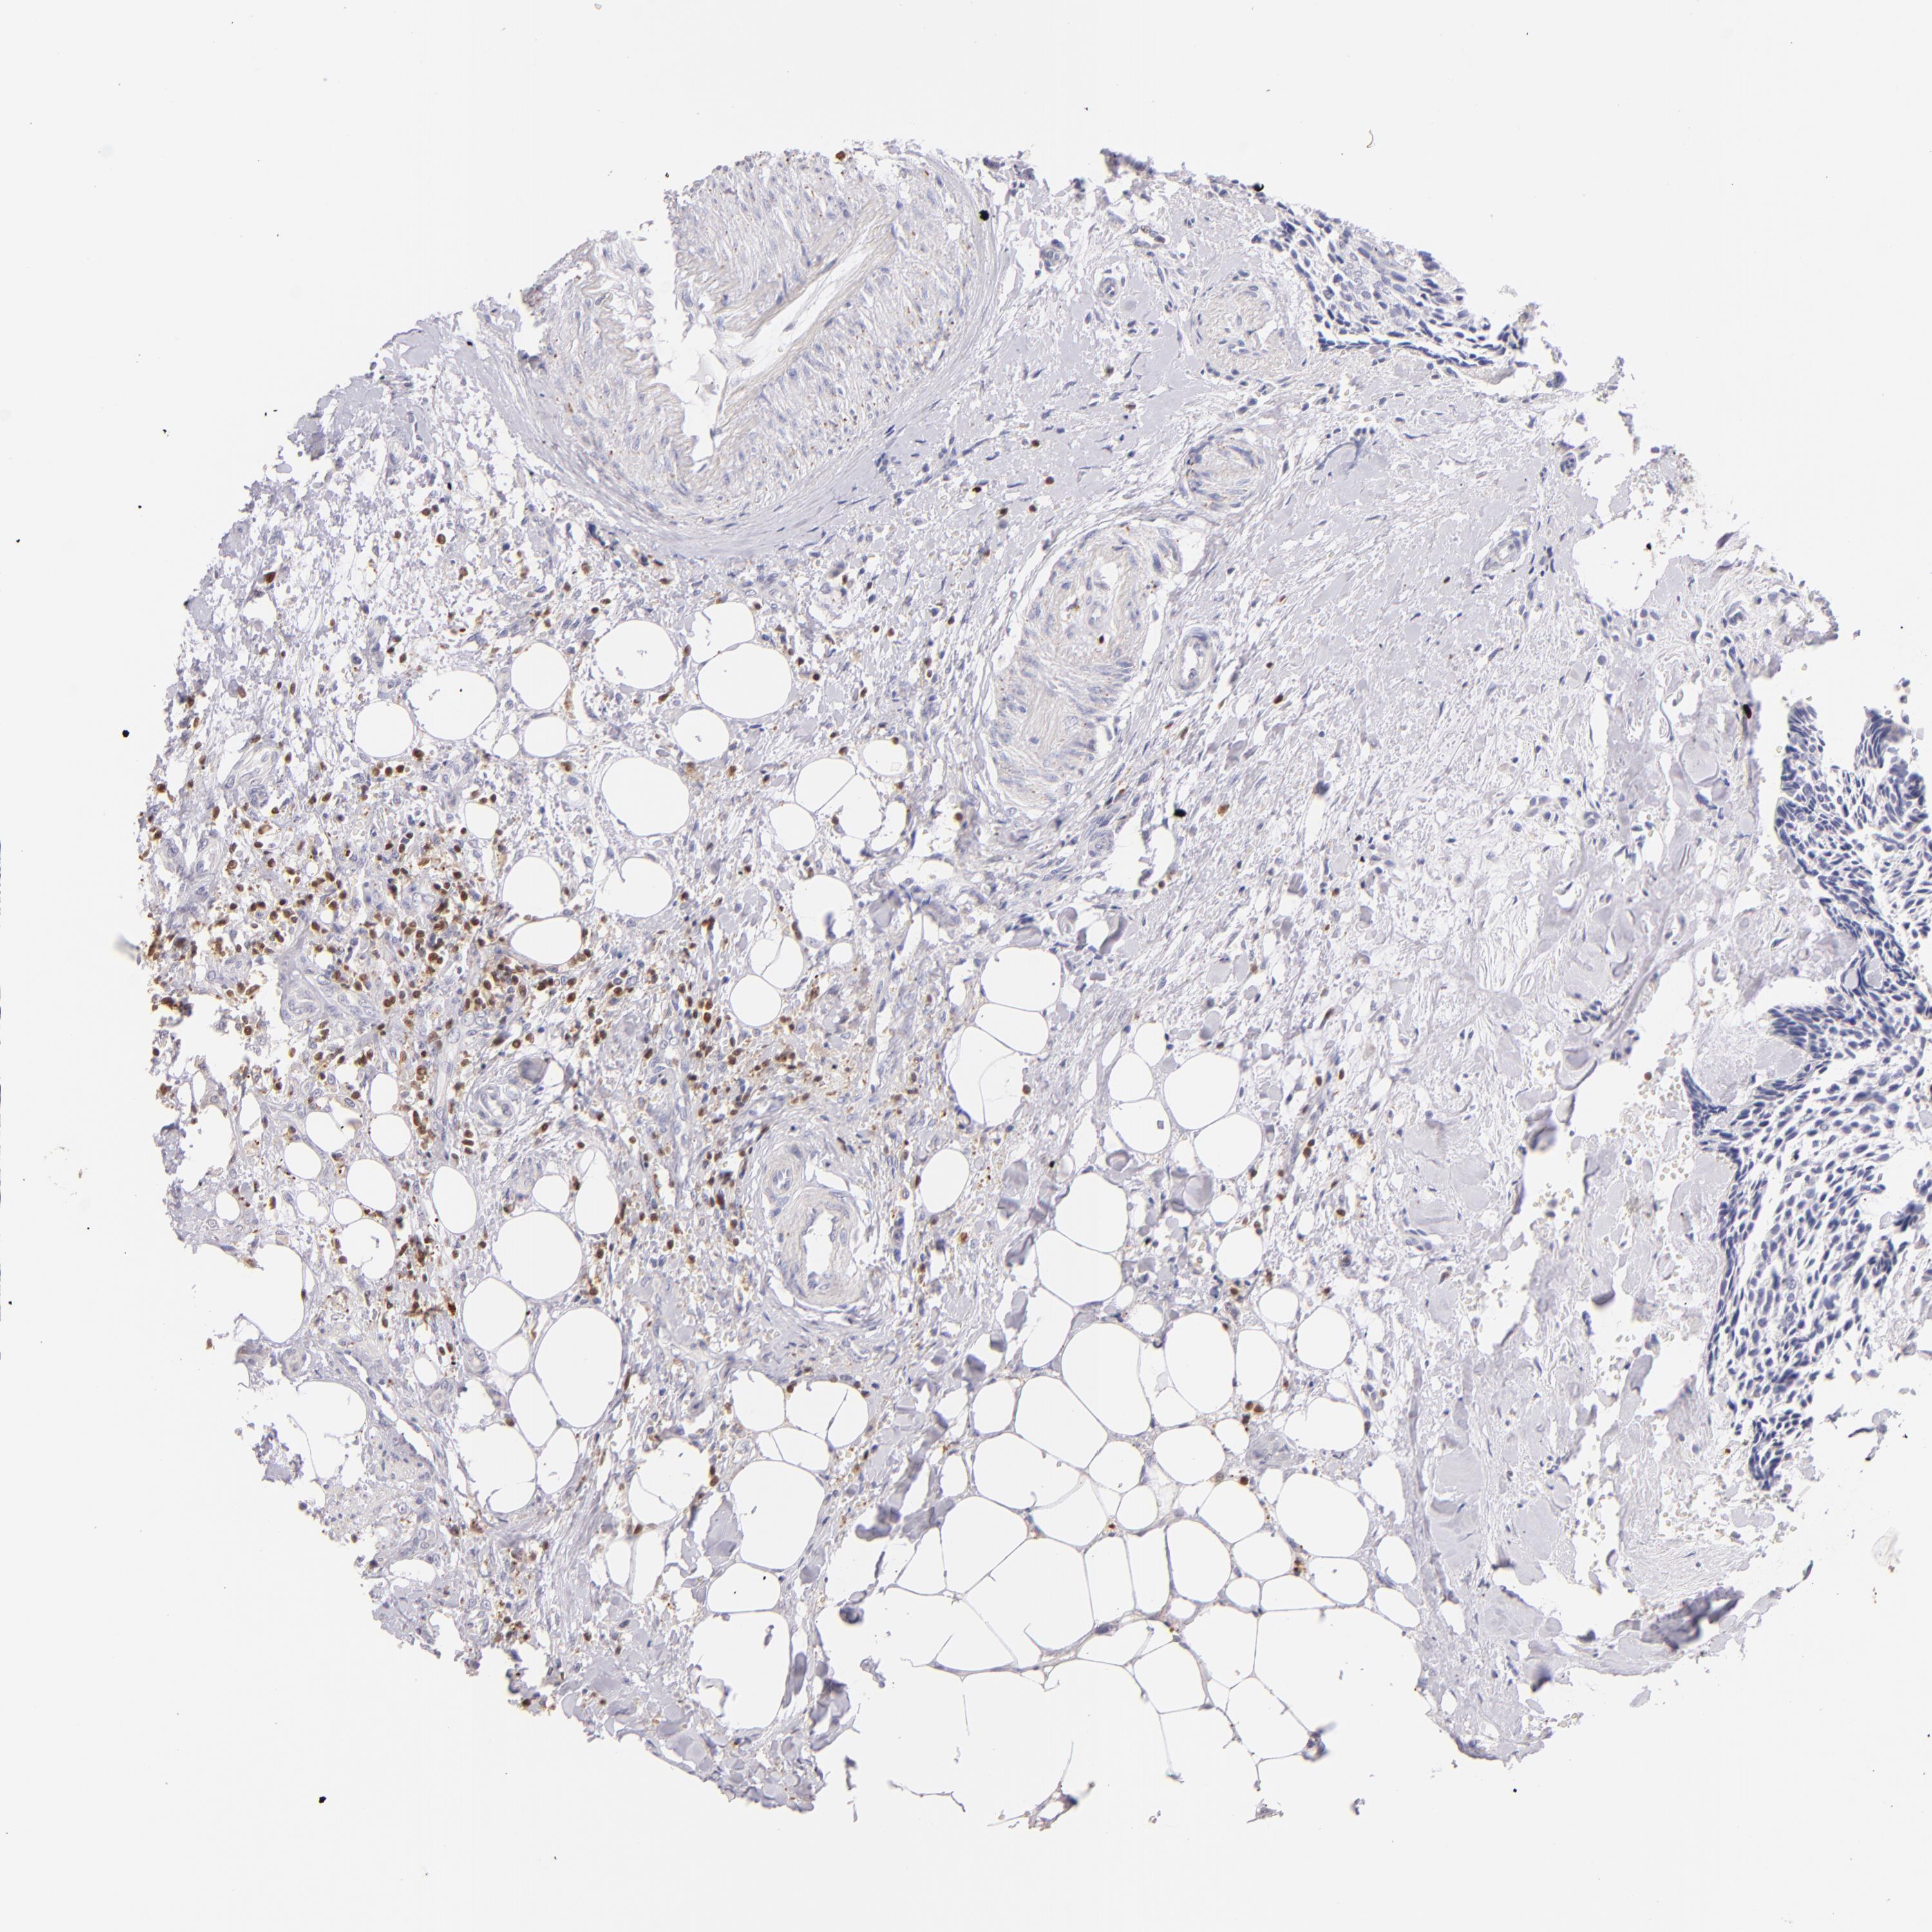

HEAD AND NECK CANCER - Protein expressioni

A mouse-over function shows sample information and annotation data. Click on an image to view it in a full screen mode. Samples can be filtered based on level of antibody staining by selecting one or several of the following categories: high, medium, low and not detected. The assay and annotation is described here.

Antibody stainingi

Antibody staining in the annotated cell types in the current human tissue is reported as not detected, low, medium, or high, based on conventional immunohistochemistry profiling in selected tissues. This score is based on the combination of the staining intensity and fraction of stained cells.

Each image is clickable and will lead to virtual microscopy that enables deeper exploration of all samples and also displays staining intensity scores, fraction scores and subcellular localization as well as patient and tissue information for each sample.

Antibody HPA003134

Antibody CAB002625

Staining

High

Medium

Low

Not detected

Intensity

Strong

Moderate

Weak

Negative

Quantity

>75%

75%-25%

<25%

None

Location

Nuclear

Cytoplasmic/membranous

Cytoplasmic/membranous,nuclear

Squamous cell carcinoma, NOS

Squamous cell carcinoma, metastatic, NOS